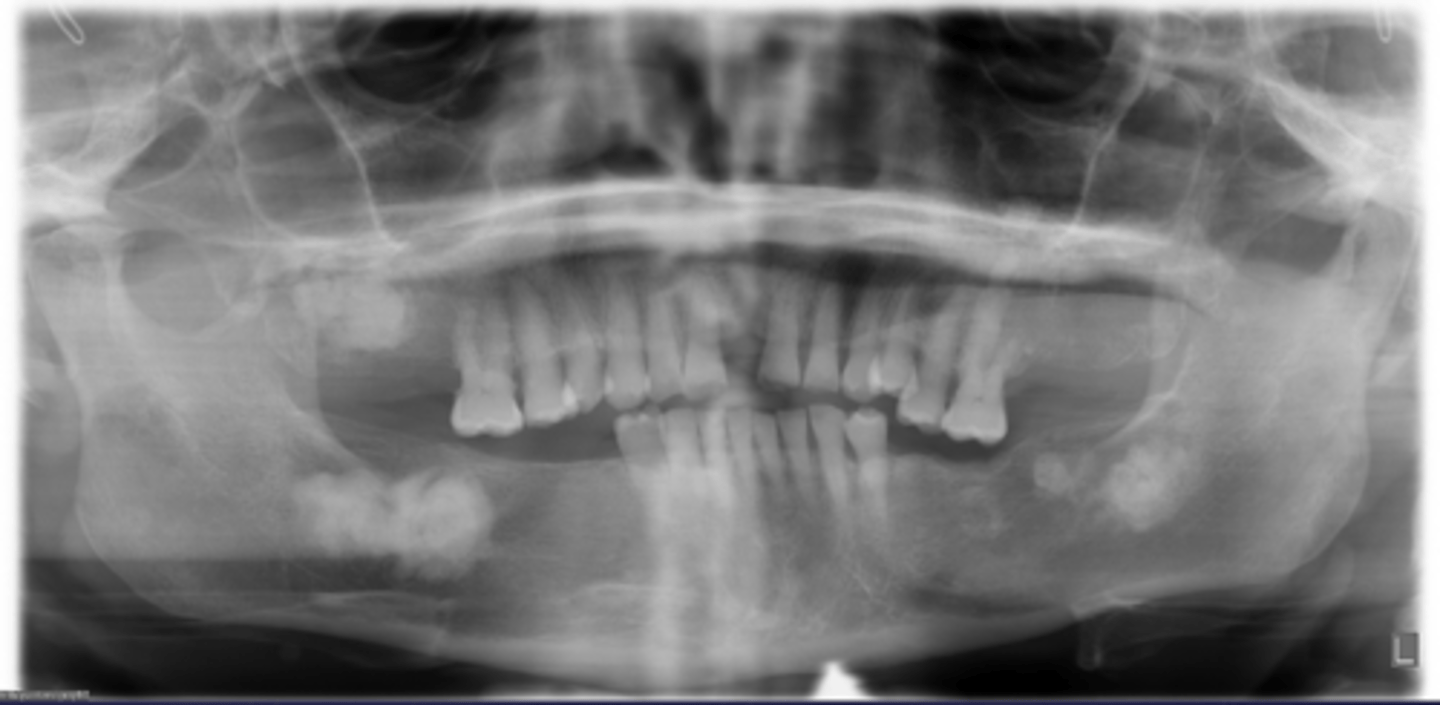

How would you describe the lesion?

- Ill defined, moth-eaten trabecular pattern in the entire mandible

- There is chronic periodontal bone loss associated with most mandibular teeth with furcation involvement and apical radiolucencies

- There is thinning of the inferior mandibular cortex.

- Can also be described as ill-defined areas of mixed radiolucent and radiopacities throughout the

mandible

What category would this lesion be part of?

Inflammation/Malignant

What would be a differential diagnosis for this lesion?

Chronic osteomyelitis

(DD: osteomyelitis, multiple myeloma)